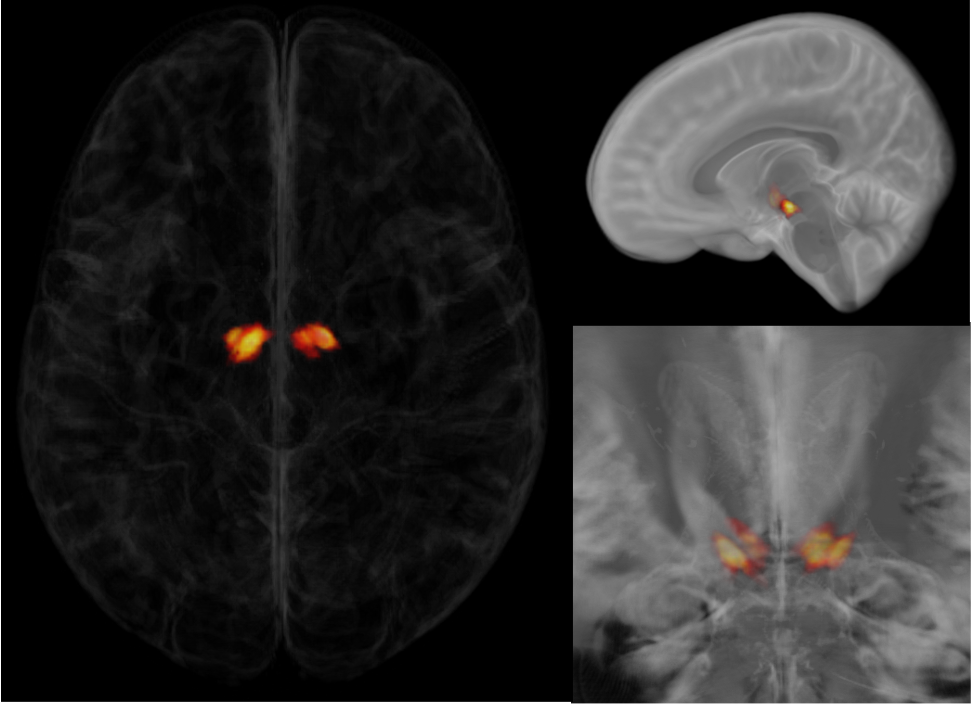

Description:Atlas of the Sub-thalamic Nucleus